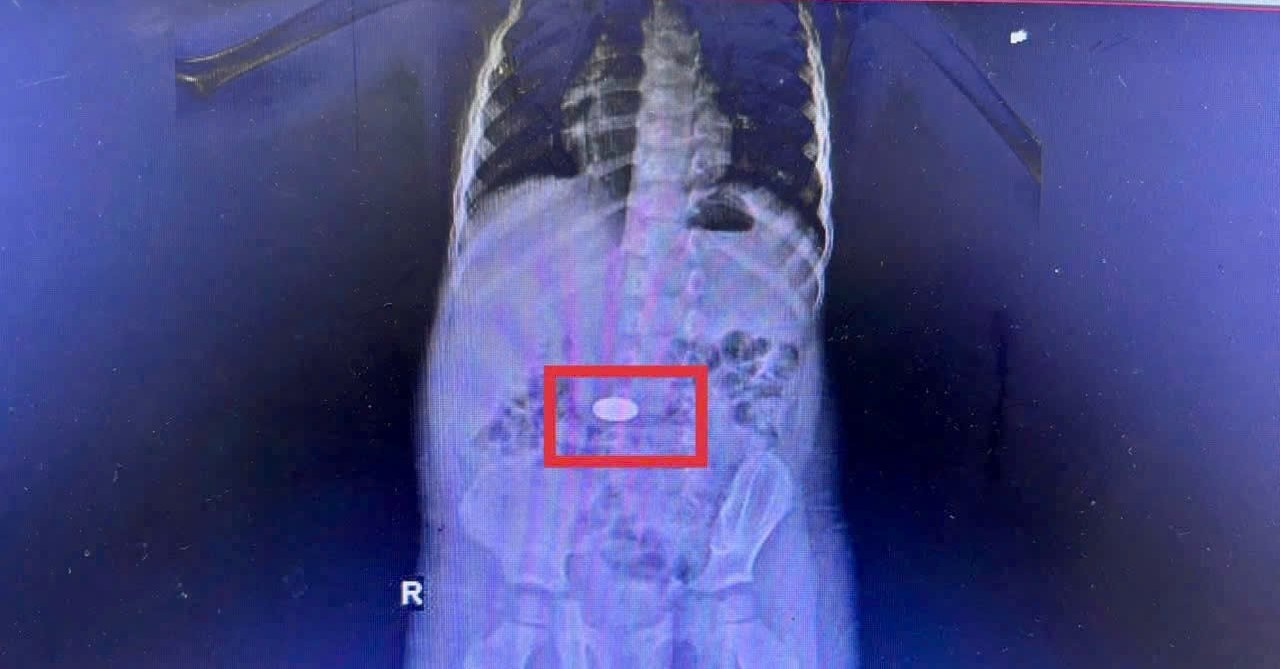

Một trường hợp điển hình là bé 3 tuổi ở xã Khánh Vĩnh, nhập viện đêm 25/11/2025 trong tình trạng quấy khóc nhiều. Gia đình cho biết buổi sáng cùng ngày bé vô tình nuốt phải đồng xu khi đang chơi. Kết quả chụp CT phát hiện dị vật nằm trong dạ dày. Các bác sĩ đã nhanh chóng tiến hành nội soi và lấy ra đồng xu vào rạng sáng 26/11/2025. Bé hồi phục tốt và được xuất viện hôm sau. Trẻ từ 1 đến 5 tuổi thường có thói quen cho đồ vật vào miệng để khám phá. Vật nhỏ, trơn như đồng xu, hạt đồ chơi, cúc áo hoặc ăn thạch, trái cây tròn và trơn như nhãn, vải… đều tiềm ẩn nguy cơ hóc cao. Phụ huynh tuyệt đối không để trẻ nhỏ chơi với những vật dụng hoặc ăn các thực phẩm này khi một mình. Khi nghi ngờ trẻ hóc hoặc nuốt dị vật, cần đưa trẻ đến ngay cơ sở y tế có đủ phương tiện nội soi để xác định và xử trí kịp thời. Việc chậm trễ có thể khiến dị vật di chuyển sâu hơn, gây biến chứng nguy hiểm và việc can thiệp trở nên khó khăn.